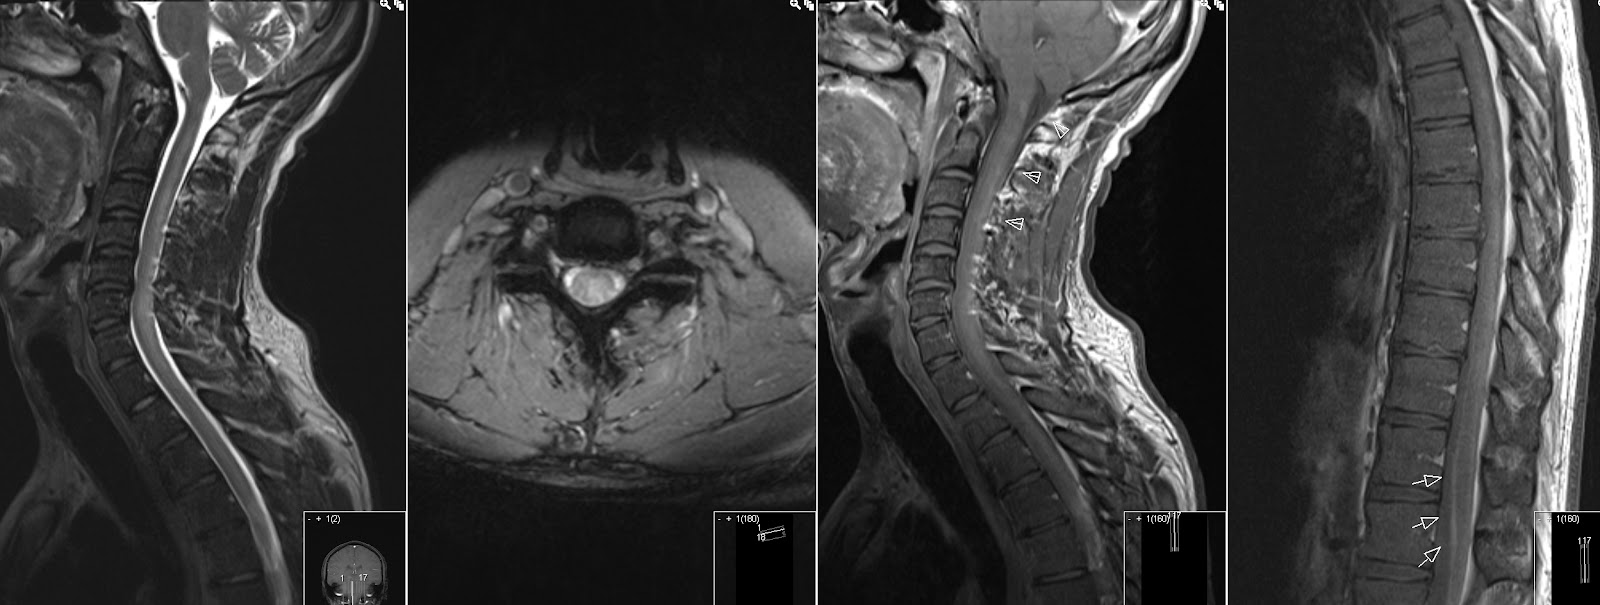

Фуникулярный миелоз симптомы

Фуникулярный миелоз симптомы 117 фото